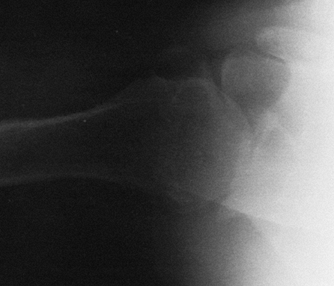

Rotator-cuff tear arthropathy if the cuff is unreconstructible (Fig. 101.12)

Figure 101.12.

Rotator-cuff tear arthropathy. There is severe superior migration of

the humeral head, and wear into the acromion and the acromioclavicular

joint. Severe glenohumeral arthritis is evident. -